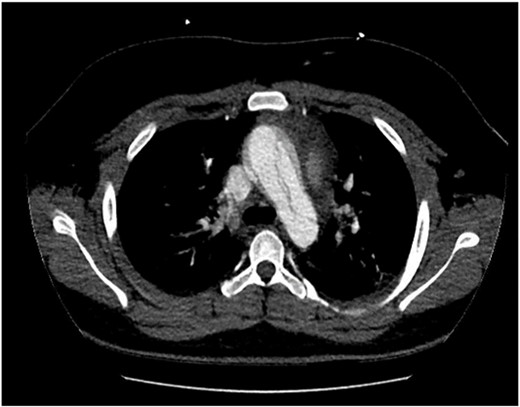

The patient was hemodynamically stable during his admission; however, worsening pain profile led to a serial electrocardiogram showing sinus rhythm with ST segment changes consistent with ischemia. There was an initial troponin rise of 245 ng/L progressing to a peak of 922 ng/L. The remaining blood panel was unremarkable. Chest X-ray showed no widened mediastinum and clear lung fields. A bedside transthoracic echocardiogram demonstrated a dissection flap with severe aortic regurgitation in the ascending aorta. Computed tomography aortogram was consistent with a Stanford Type A aortic dissection extending from the aortic root to the bifurcation of the common iliac arteries (Figs 1 and 2). There was involvement of the right brachiocephalic artery and right common iliac.

Computed tomography aortogram Axial Image of Stanford Type-A Aortic Dissection.

Computed tomography aortogram Axial Image of Stanford Type-A Aortic Dissection extending into arch and descending thoracic aorta.